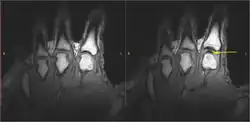

Static images of the hand in the resting phase before cracking (left). The same hand following cracking with the addition of a post-cracking distraction force (right). Note the dark, interarticular void (yellow arrow).